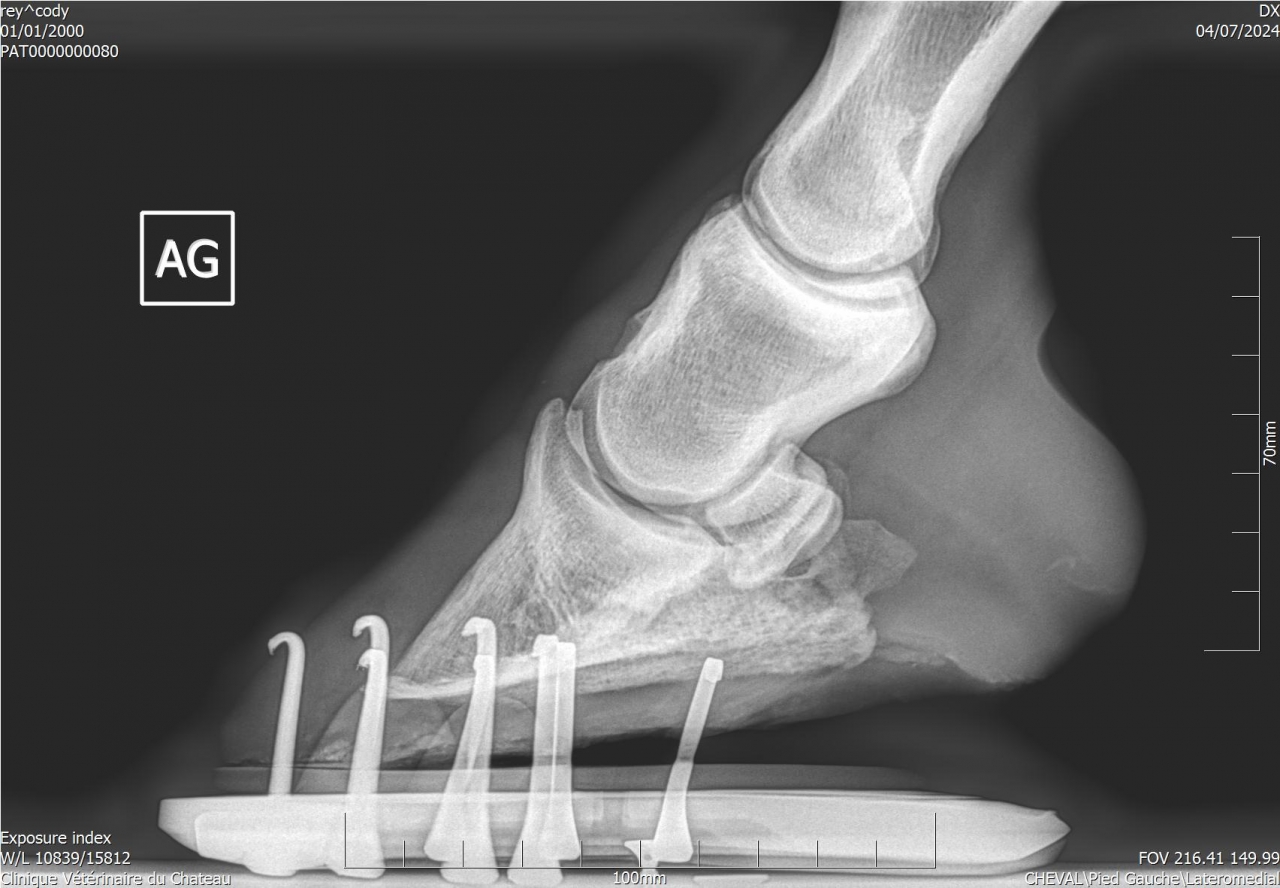

| Dire merci | Je fais un sujet à part pour donner des nouvelles ![]() J’ai fait passer un autre véto pour un 2ème avis. Au début il pensait à un abcès très profond, emplacement détecté avec la pince à sonder. Il a ensuite fait des radios : si j’ai bien compris, la 3ème phalange appuie sur la sole Il y a également de l’arthrose ... Le traitement pour le moment : anti inflammatoires et hipposandales en attendant de pouvoir referrer, et changer de maréchal ferrant. Apparemment il existerait un traitement au laser, le véto va se renseigner. Cody a fait une fourbure l’année dernière, des radios ont été faites à ce moment. J’ai aussi refait des radios de contrôle cette année, il restait une légère bascule de P3. |

| Dire merci | Radios de mai 2023![]() ![]() Radios de juillet 2023 ![]() ![]() Radios d'août 2024 ![]() ![]() |

| Dire merci | Il y a quand même de jolies bascules, il doit pas être bien c'est sûre. Les degrés de bascule t'ont été donnés? Pour moi il y a urgence à trouver un bon maréchal, qui va travailler avec les radios, mais ça va mettre plusieurs mois à "rentrer dans l'ordre" si pas d'autres crises inflammatoires et nouvelles bascules, ça se compte en plusieurs mois voir année. Et malheureusement une surveillance constante. |

| Dire merci | J'ai eu le collègue du véto au téléphone : pas de risque immédiat que la phalange perce la sole il reste 1 cm. La 3ème phalange appuie sur la sole, il y a nécrose. La pointe ne risque pas de casser. Je viens de commander 2 hipposandales Cloud. Il faut que je trouve quelqu'un pour déferrer Cody et éventuellement parer l’autre antérieur. Message édité le 22/11/24 à 20:31 |

| Dire merci | Voici les dernières radios :![]() ![]() ![]() |